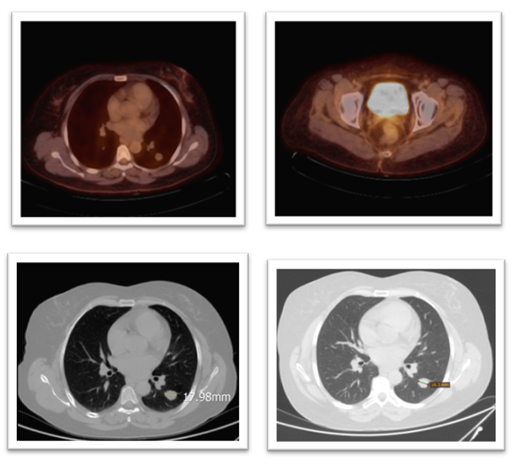

Restaging imaging was performed three months after the completion of radiotherapy and initial systemic therapy. In October 2023, a whole-body PET-CT scan demonstrated a complete metabolic response to treatment. The previously noted pelvic mass showed no discernible FDG uptake or residual tumour on PET, and multiple lung metastases were inactive and stable in size. Essentially, there was no visible evidence of active disease on the post-therapy scans. Complete remission was achieved approximately one year after the patient’s initial presentation. (Figure 8) Clinically, the patient’s symptoms resolved, her pelvic pain disappeared, and she had no respiratory symptoms or other complaints.

Figure 8: Top R&L: PET scan shows no metabolic activity of the previously seen avid lesions in the lung and pelvis, particularly the previously reported Right femoral head. Bottom Left: CT chest in May 2024 compared to bottom R CT in April 2025, showing a reduction in size of the target lesion in the left lung from 17.98mm to 16.3 mm.

Given this remarkable response, a decision was made to continue maintenance therapy to reduce the risk of relapse. From late 2023 onwards, the patient has remained on goserelin (3.6 mg monthly) to maintain a postmenopausal hormonal state, bicalutamide 50 mg daily, and pazopanib 800 mg daily. The patient continued on this maintenance regimen with ongoing surveillance.

Regular follow-up imaging was performed every 3-4 months. As of her last assessment in Aug 2025, approximately > 24 months after completing the initial therapy, the patient remains in complete metabolic remission. Serial computed tomography (CT) scans of the chest, abdomen, and pelvis showed no evidence of recurrent or new disease. Clinically, the patient was doing well and resumed normal activities. She will continue on the combined hormone-targeted maintenance for now, with periodic re-evaluation and imaging. Long-term surveillance is planned, as uterine LMS carries a significant risk of recurrence, even after sustained remission.